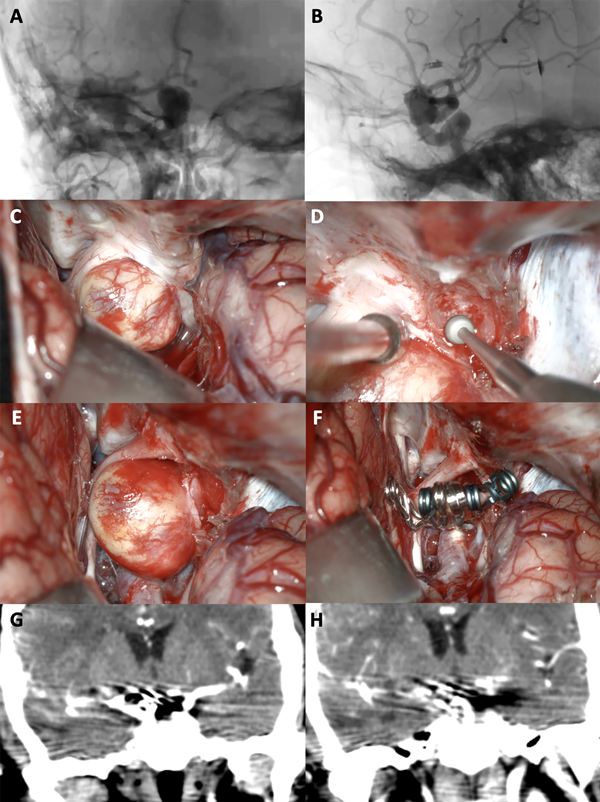

Figura 3. A-B: Se aprecia una arteriografía cerebral con reconstrucción tridimensional que evidencia un aneurisma carótido oftálmico izquierdo. C-F: Fotografías intraoperatorias; observamos la apertura de la fisura silviana con la presencia de la cisterna óptico-carotidea en la profundidad: es visible el saco aneurismático. Posteriormente se realizó un fresado del techo del canal óptico, con lo cual se logró una adecuada exposición del cuello del aneurisma. Se muestra la exclusión del aneurisma con dos clips semi curvos. G-H: Imágenes de angio tomografía post operatoria que evidencia la exclusión completa del aneurisma.